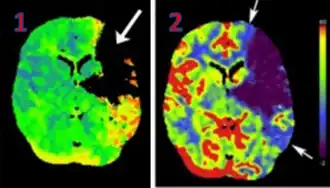

![]() CT perfusion with flow and volume maps in cerebral infarction | |

CT Perfusion plays an important role in the assessment of Acute Ischemic Stroke. It is used to create maps of blood flow, blood volume, and mean transit time to assess the tissue and to differentiate between the core and penumbra in stroke.[3]